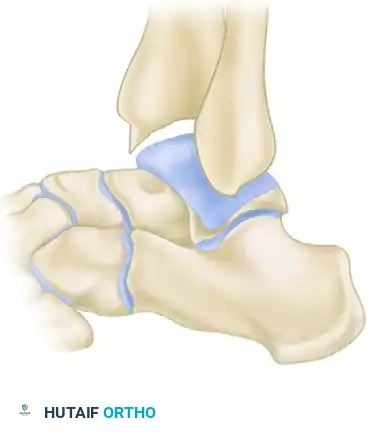

Osteochondritis Dissecans (OCD) of the Talus

During the arthroscopic evaluation of impingement syndromes, the surgeon must meticulously inspect the talar dome for concurrent Osteochondritis Dissecans (OCD) lesions. These lesions are focal areas of subchondral bone necrosis and secondary cartilage damage, frequently resulting from the same traumatic inversion mechanisms that cause soft tissue impingement.